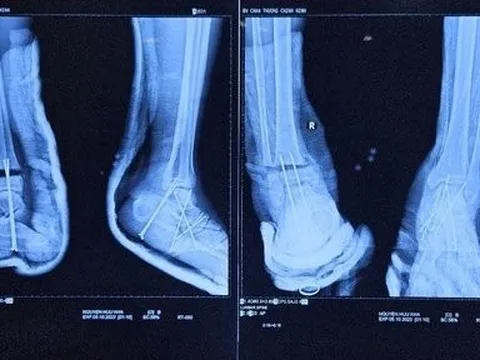

Hy hữu bệnh nhân bị đứt lìa cổ chân được phẫu thuật kịp thời

Ngày 14/10, bệnh nhân ở Bến Tre bị máy cắt cỏ cắt đứt lìa cổ chân, được bác sĩ phẫu thuật kịp thời.